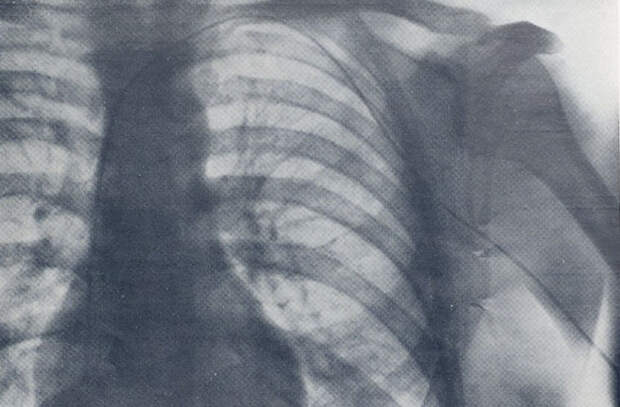

Рентген, на котором виден катетер, введенный доктором в свое тело

Вернер Форсман рассматривает рентгеновские снимки своего тела с катетером